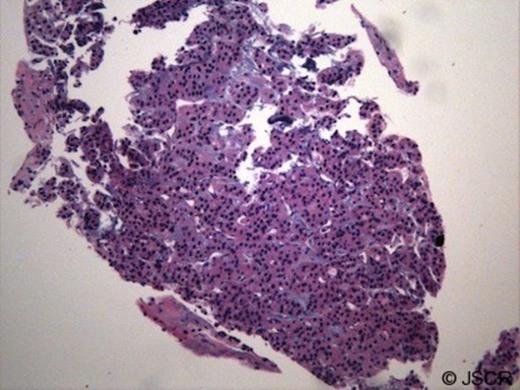

Following surgery, the patient recovered uneventfully and was discharged. Final pathology of the thyroid gland showed follicular carcinoma with Hurthle cell features [Figure 5].

Microscopic examination of resected thyroid gland (H and E stain) demonstrates invasive thyroid follicular carcinoma with hurthle cell features and extensive angioinvasion.

There was both capsular and extensive angioinvasion. The thyroid tumour was found within the lumen of SVC causing complete occlusion. The patient has since undergone radioactive iodine ablation therapy.